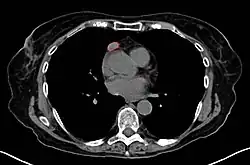

Work-Up

• CT scan

• Thymoma typically presents in the anterior/superior mediastinum